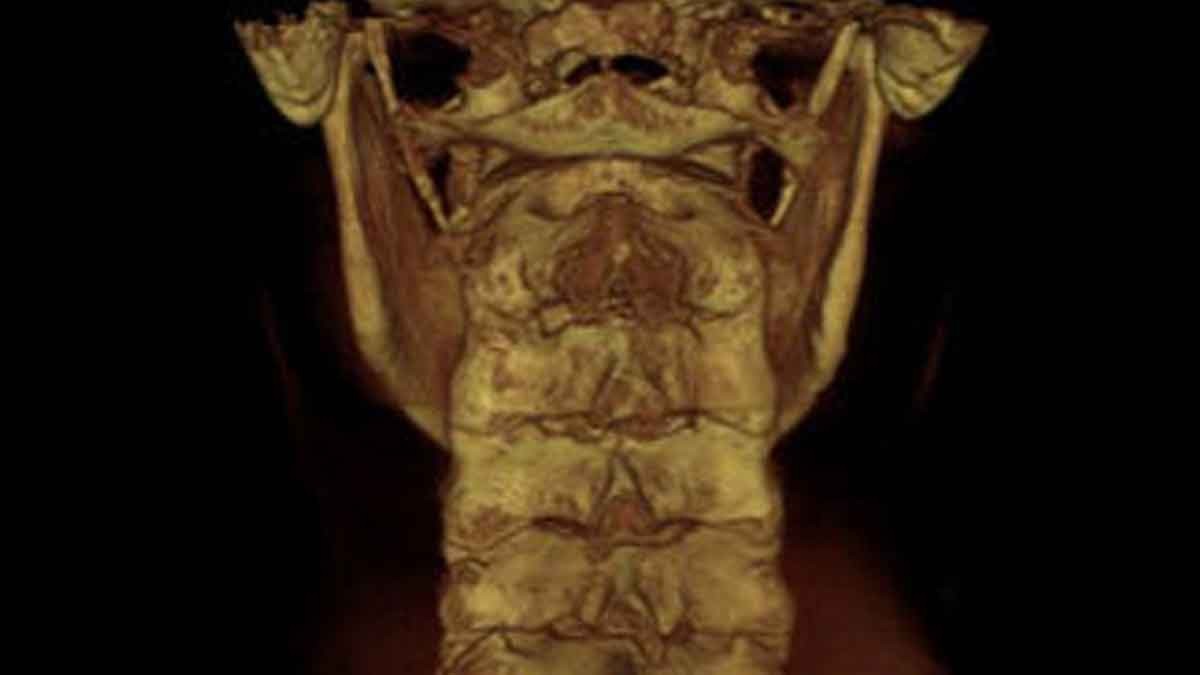

SAGITTAL VIEW OF UPPER CERVICAL SPINE

This view allows the doctor to assess the neural canal, the foramen magnum, and the longitudinal direction of the joints on the left and right that are on the bottom of the skull called the occipital condyle.